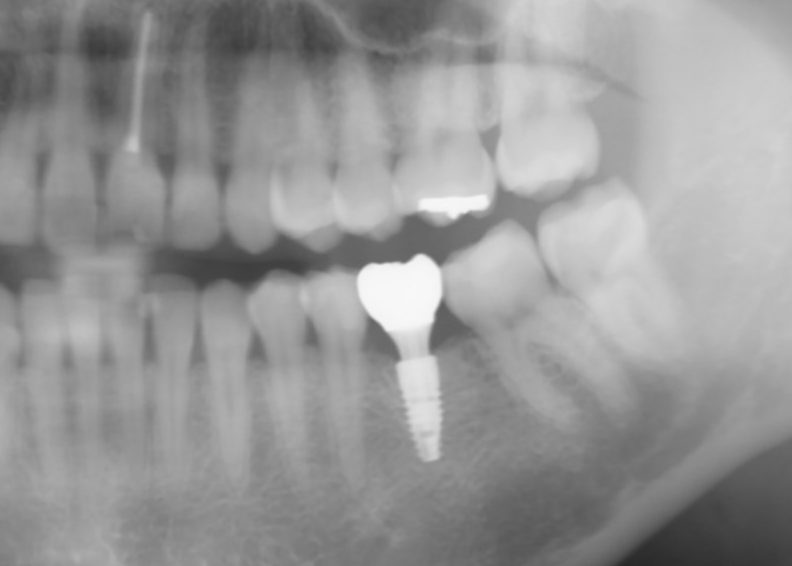

完成した状態です。

無事、終了しました(^^)

他にも治療が必要な部位はありますが、先ずはご希望の治療をしっかりと行いました。